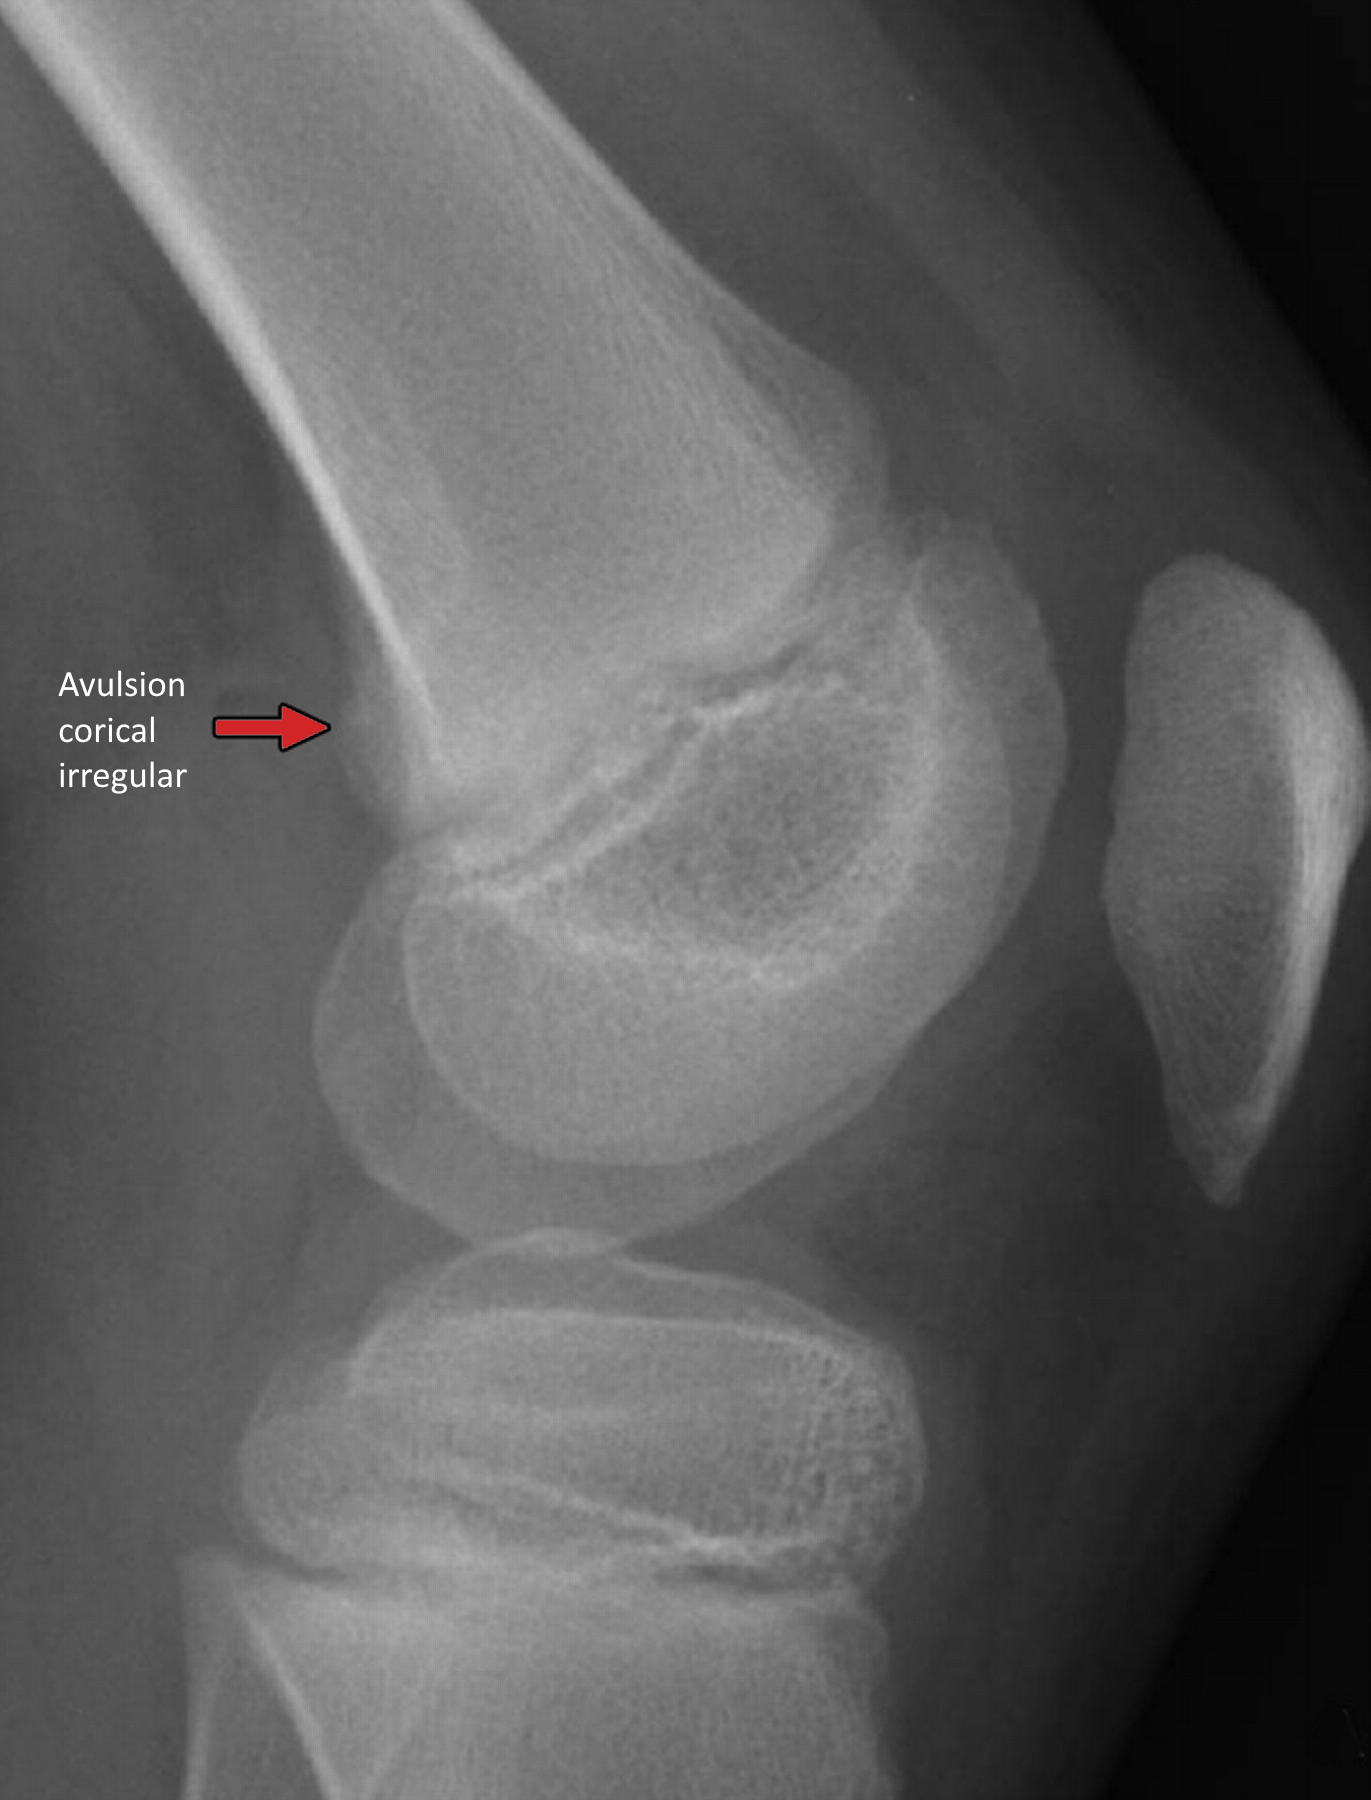

📷 Radiografía (RX)

En la radiografía simple, el desmoide periostal se observa como una lesión radiolúcida cortical con una base esclerótica bien definida. El borde puede ser irregular o en “cepillo”, lo que en ocasiones puede simular agresividad. Es fundamental destacar que no hay destrucción ósea agresiva, ni reacción perióstica franca, ni masa de partes blandas asociada en los casos típicos.

Figura. Radiografía lateral de desmoide cortical en la cara posterior del fémur distal.